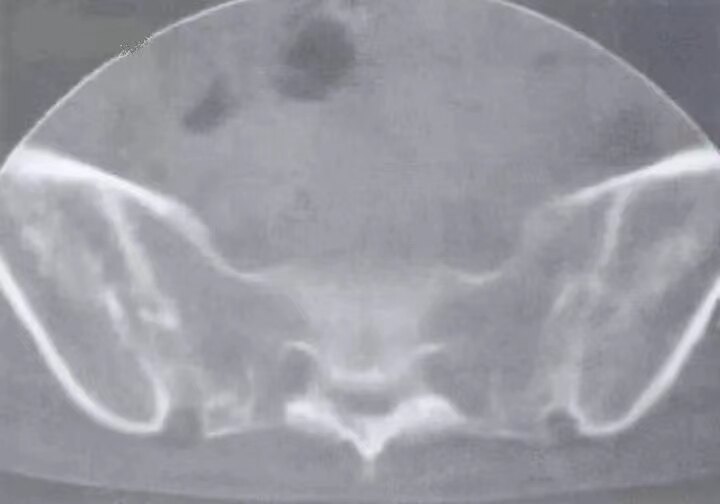

图注:双侧骶髂关节骨质破坏,关节间隙消失,骨性强直。双侧髋关节面侵蚀,轮廓粗糙不光滑,以髋臼明显,骨盆疏松。

图注:CT示双侧骶髂关节破坏,多发小囊变,关节间隙消失,骨性强直,骨质疏松。